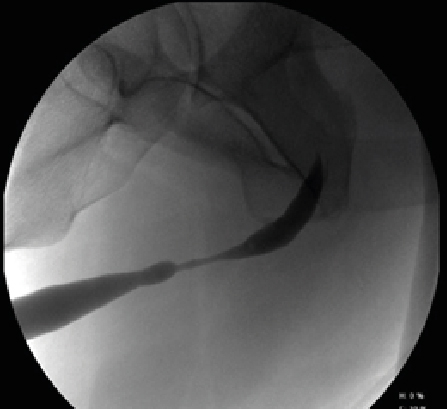

Retrograde urethrography is a very dynamic study, which must be taken into account when acquiring images, especially when sending still images, a common error is the leakage of contrast towards the skin (Figure 1) avoiding using a Foley catheter at the level of distal urethra to retain the contrast, however it can condition trauma [1]. Another common error is the ignorance of ideal projections for evaluation of the urethra (Figure 2), for example the Lauenstein projection, which is more useful for evaluating the hip. The imaging with a lack of contrast between the structures (Figure 3), which can be modified during and after the acquisition. It should be noted that on some occasions, in case of doubt, images will be taken from two different x-ray directions.

Figure 2:  AP Projections with Oblique Taking of the Penis, Avoiding Adequate Visualization of the Urethral Route